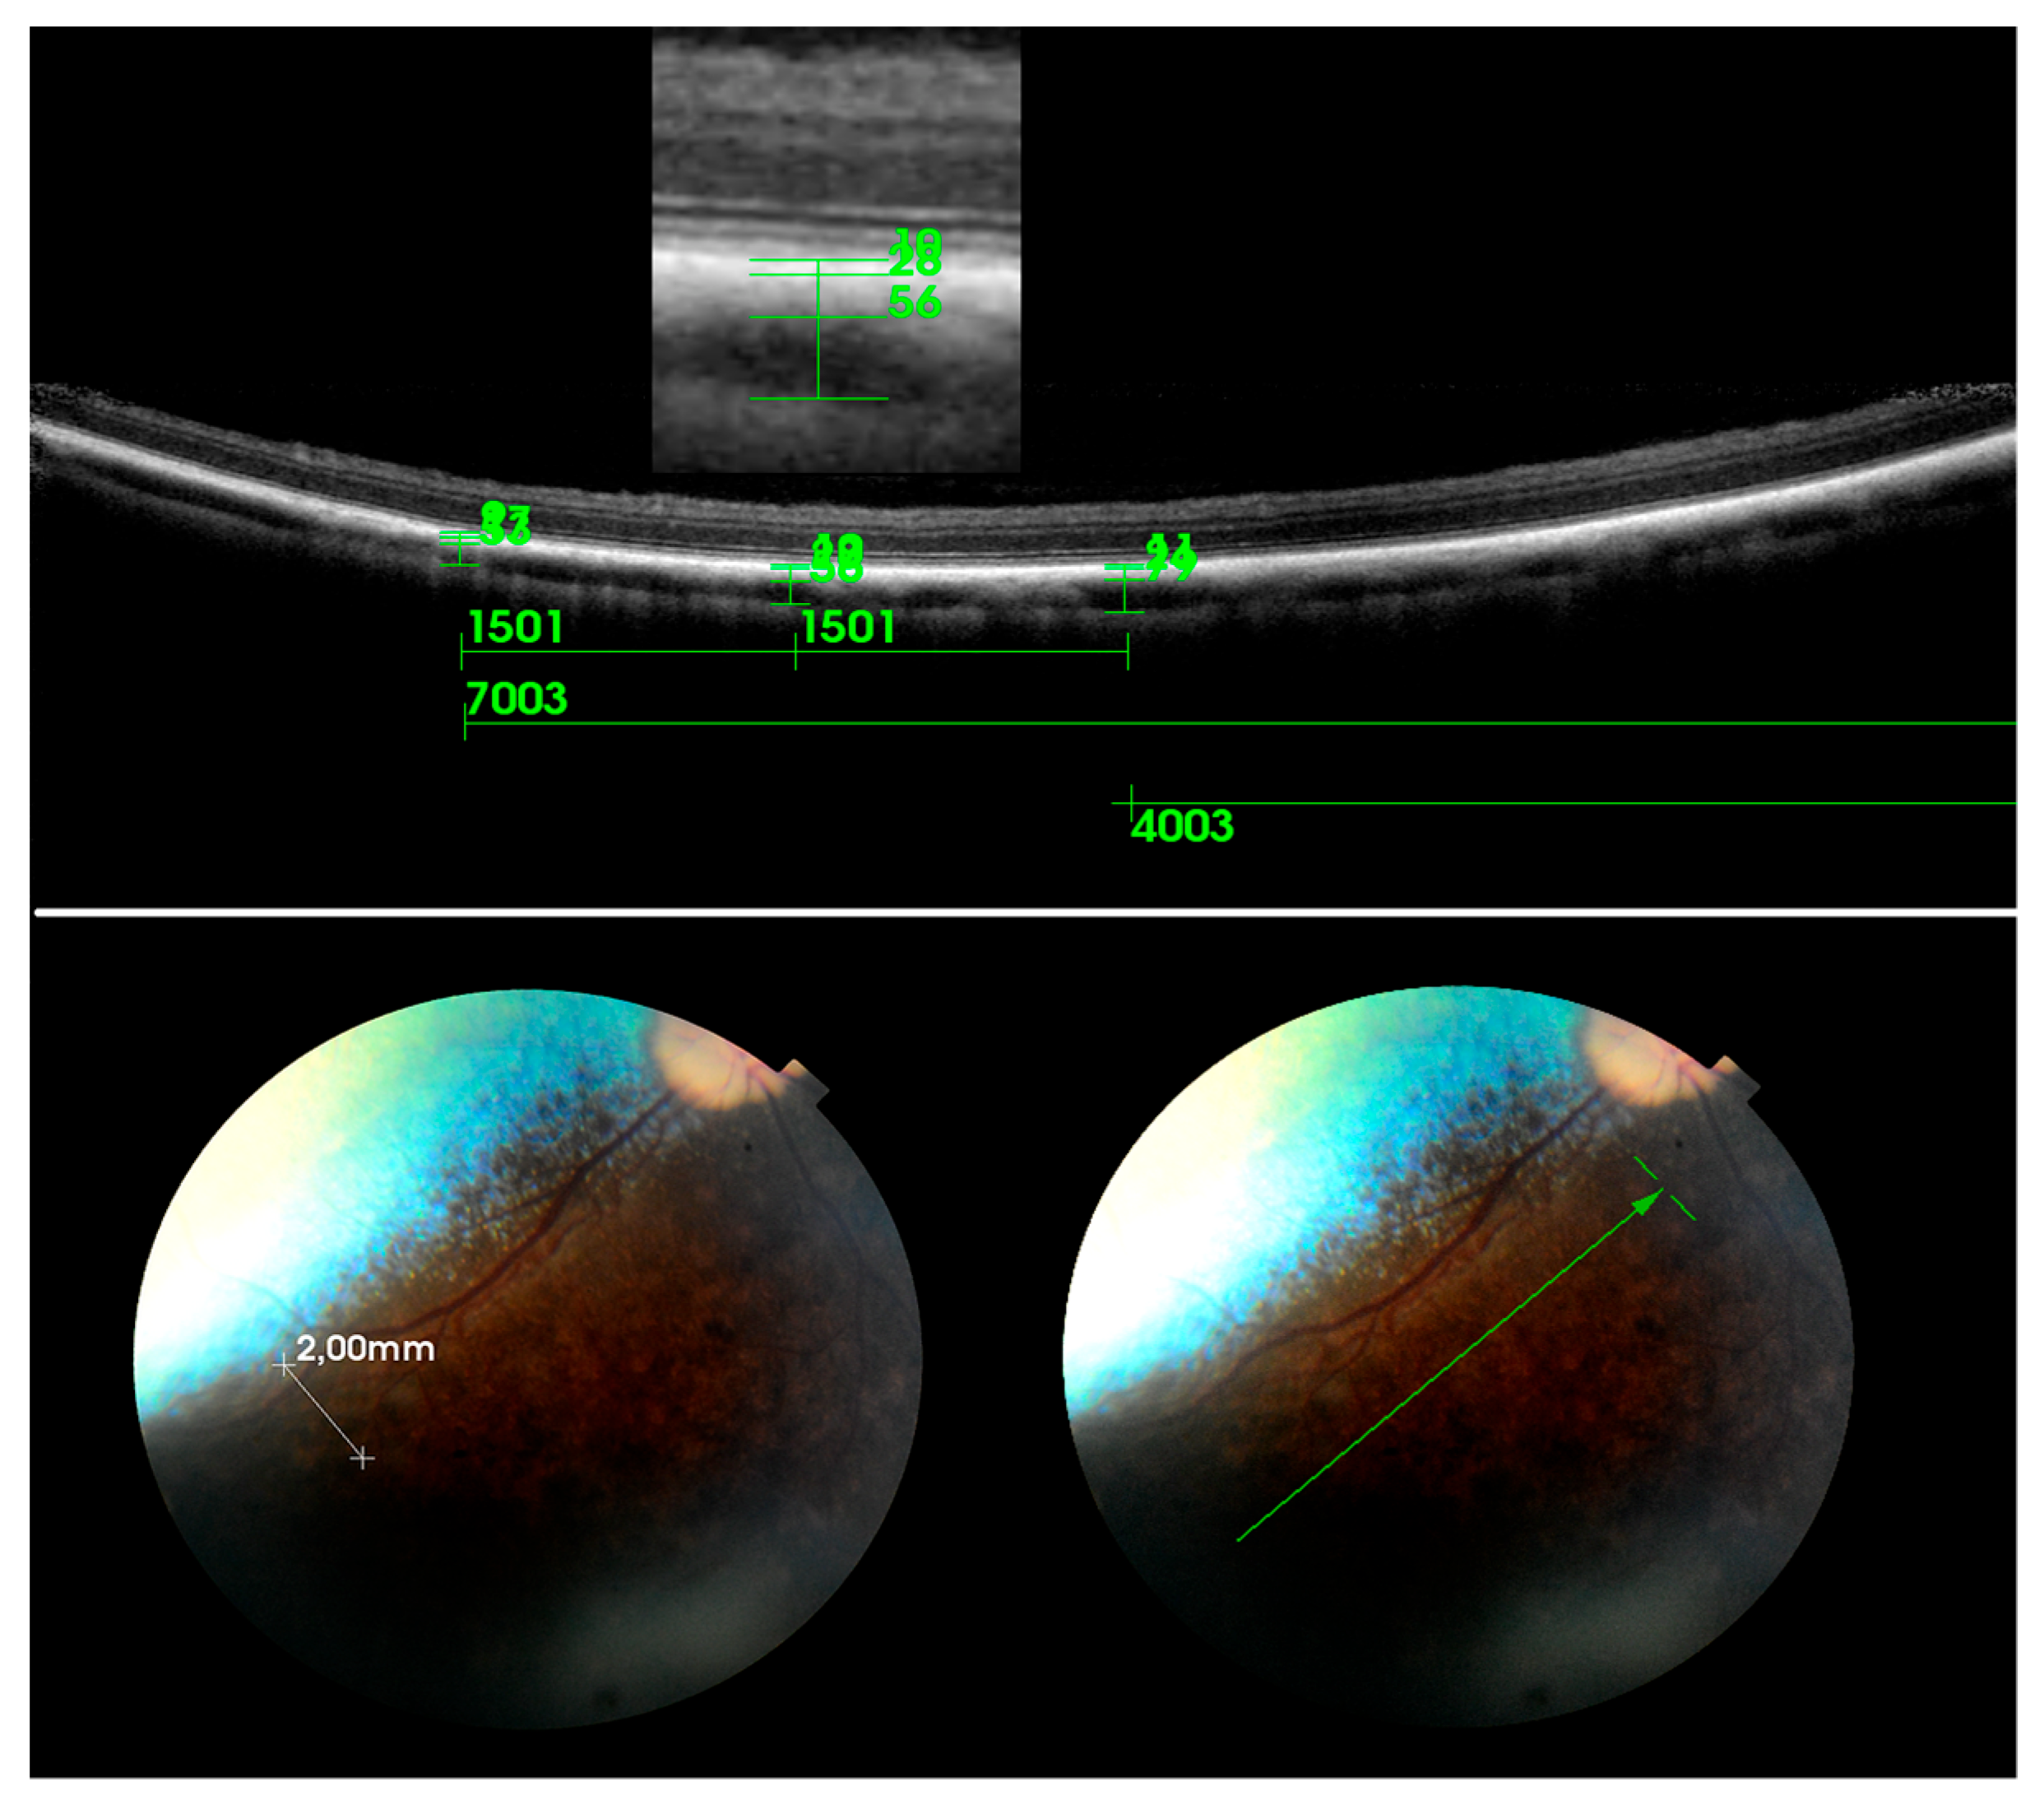

3. Results